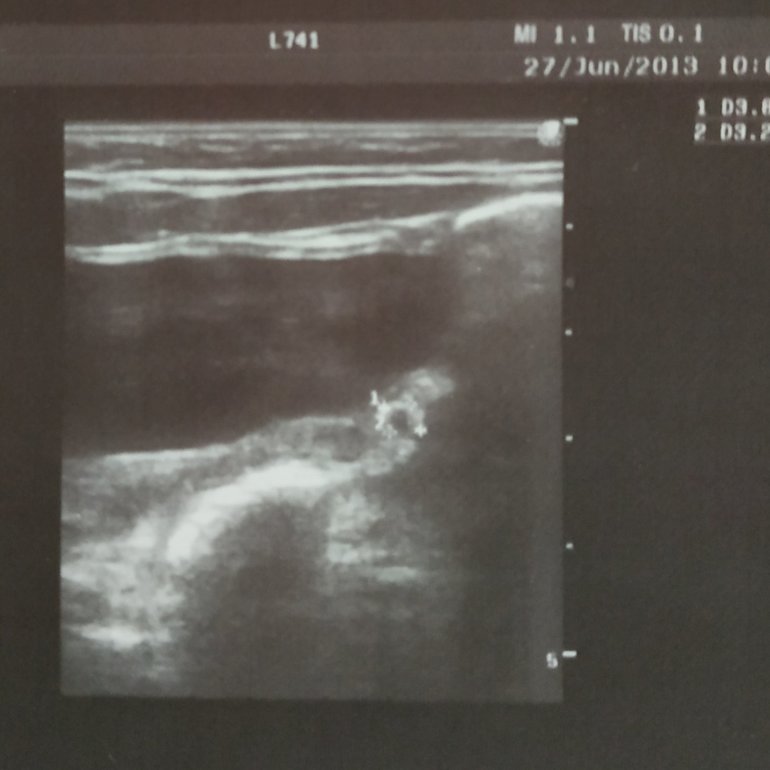

в 2 месяца, 3*4 мм:

На последующих узи не видели кисту (возможно просто не искали, попрошу в следующий раз посмотреть это место внимательнее).